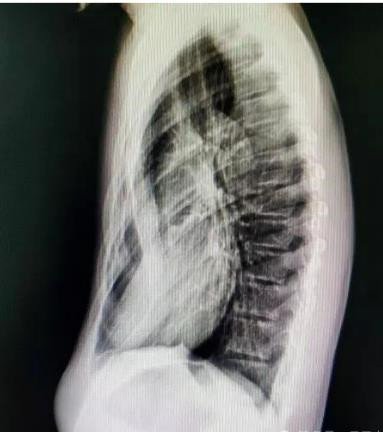

癥狀:胸骨及兩側(cè)肋骨向內(nèi)凹陷,形成 “漏斗狀” 畸形,幼兒期可能癥狀較輕,青春期隨著身高快速增長,凹陷會逐漸加深,嚴(yán)重時胸骨可貼近脊柱。

若發(fā)現(xiàn)孩子胸口有凹陷,及時帶娃到胸外科就診,通過胸部 X 線、CT 掃描、肺功能測試、心臟超聲等檢查,明確凹陷程度和心肺受壓情況,避免延誤干預(yù)時機。